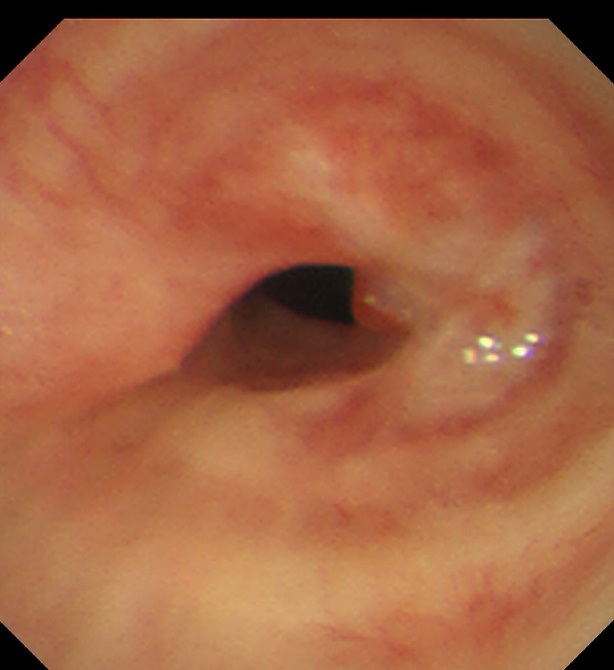

气管下段狭窄激光治疗+Y型硅酮支架植入后

术后患者呼吸困难等症状得到了立竿见影的缓解,术后第二天复查支气管镜可见支架在位良好,管腔通畅。大大改善了患者的生活质量,患者于术后第三天下午顺利出院。